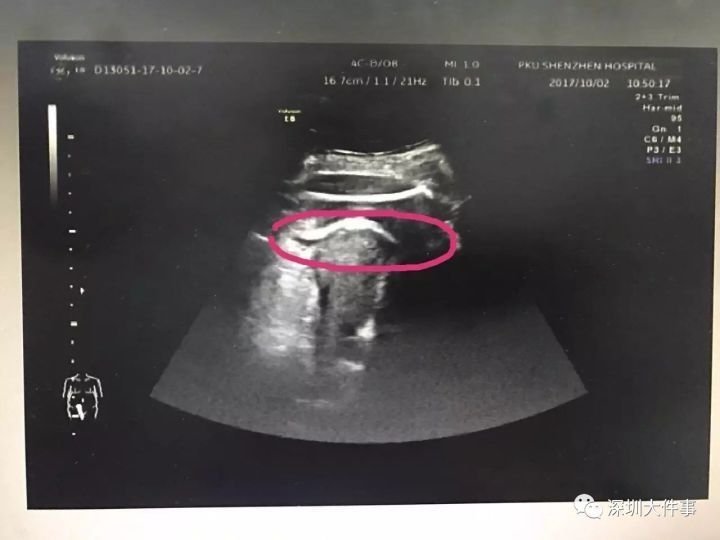

張姓婦人抵達醫院後,急診室人員見她痛得滿臉蒼白,馬上替她做檢查,據醫院檢測,當時張姓婦人的脈搏、呼吸、血壓等生命狀況都不太穩定。經急診室醫生初步判斷,懷疑張姓孕婦是子宮破裂,再由醫師進一步檢查後,雖沒有找到子宮的裂口,但是從超音波可以看到,小寶寶的腿已經在子宮上踢開了一個大洞,並進入了腹腔,大腿根部正卡在子宮壁上。

▼超音波可以看出寶寶的腳踢破子宮。(圖/翻攝深圳大事件)

▼母親子宮上被寶寶踢出一個大洞。(圖/翻攝深圳大事件)